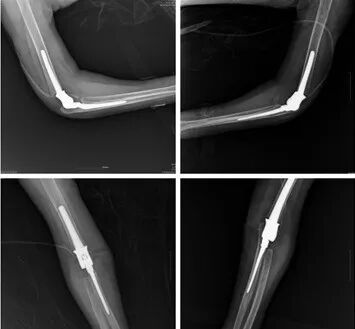

患者王女士,48歲,25年前診斷為類風(fēng)濕關(guān)節(jié)炎。3年前病情突然加重,膝關(guān)節(jié)和肘關(guān)節(jié)完全不能活動(dòng),生活幾乎不能自理。

經(jīng)人介紹,王女士找到了省級(jí)知名骨科專家、邦爾骨科集團(tuán)首席專家、嘉興邦爾骨科醫(yī)院院長(zhǎng)趙凱教授。趙凱教授為王女士會(huì)診后,決定應(yīng)用3D打印技術(shù)為患者定制專屬的肘關(guān)節(jié)假體,進(jìn)行“雙側(cè)人工肘關(guān)節(jié)置換術(shù)”。

患者術(shù)后功能恢復(fù)良好,相比于普通的肘關(guān)節(jié)置換手術(shù),3D打印技術(shù)能夠縮短手術(shù)時(shí)間,手術(shù)更加精確。

患者術(shù)后雙肘關(guān)節(jié)的正側(cè)位片